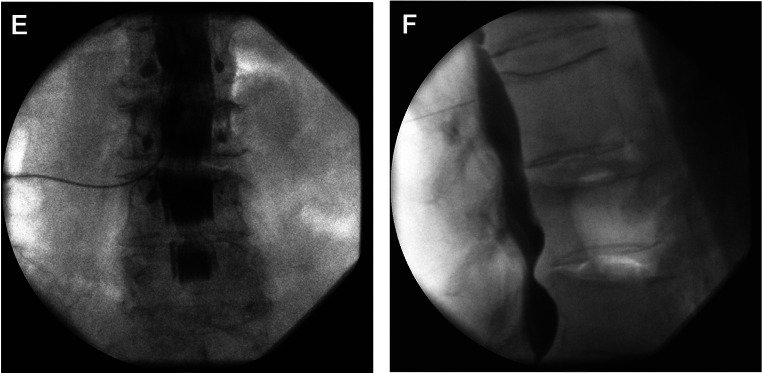

Purpose of review: The purpose of this educational review is to describe the contrast spread patterns that indicate accurate needle placement in the epidural space and spread patterns associated with erroneous needle insertion.

Recent findings: Epidural injections are minimally invasive and commonly used for patients with acute and chronic back pain that does not respond to conservative management. Imaging with contrast is frequently used during this procedure to improve accuracy and reduce adverse events. Contrast spread patterns are an important tool that can help identify where the needle is placed and whether the placement is accurate. Despite this, there may be discrepancies in the interpretation of spread patterns which ultimately reduce the utility of contrast. Inaccurate needle placement may result in intrathecal/subarachnoid, subdural, fascial, or retrodural space of Okada injections. The correct interpretation of contrast spread patterns on imaging is crucial for confirming accurate epidural needle placement. Furthermore, understanding contrast patterns of improper needle placement can prevent adverse events that result from injection outside of the epidural space.